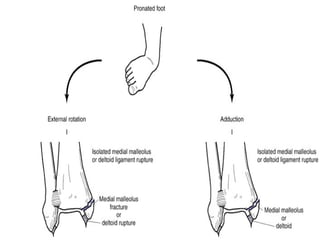

LAUGE HANSEN”S

    Associates specific fracture patterns with

mechanism of injury

    Two-term scheme

1.   Position of foot

Supination (lateral)

Pronation (medial)

1.   Direction of force

Adduction / abduction

External rotation

Dorsiflexion

ADDUCTION INJURY

   Traction on the lateral structures

# forcible inversion of the plantar flexed foot

> ant talo-fibular tear

# forcible inversion at right angle

> tear of all 3 lateral ligaments or

lateral malleolus fracture

> compression injury of the medial

malleolus causing vertical fracture +/-

depression of articular surface

EX ROTATION INJ WITH INF

TIBIO-FIBULAR JT

DIASTASIS

   Also known as PRONATION-EXTERNAL

ROTATION FRACTURE

   Three types –

# isolated fracture of med malleolus

# partial diastasis of the inf tibio-fibular

joint

# complete diastasis of the inf tibio-

fibular joint